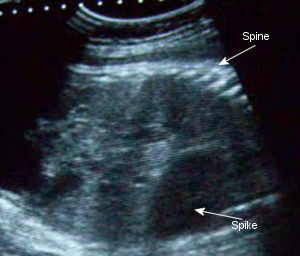

February 16th: Fastest, most pointless appointment I’ve had. It was really quick and all Dr. C. did was give me an ultrasound. Emily’s head is very much stuffed in my pelvis and he checked her heart, legs, and spine. He even showed me that she’s still a girl. I didn’t get a pelvic exam, which, even though I despise them, would have been nice to have since I’m feeling a little different down there and would have liked to know if I’m dilated. Oh well. I’ll run the questions I had for Dr. C. next Monday.